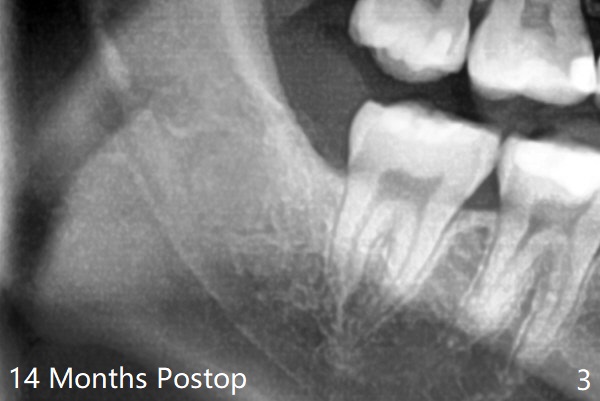

The lower 3rd molar sockets heal in 14 months (Fgi.3).